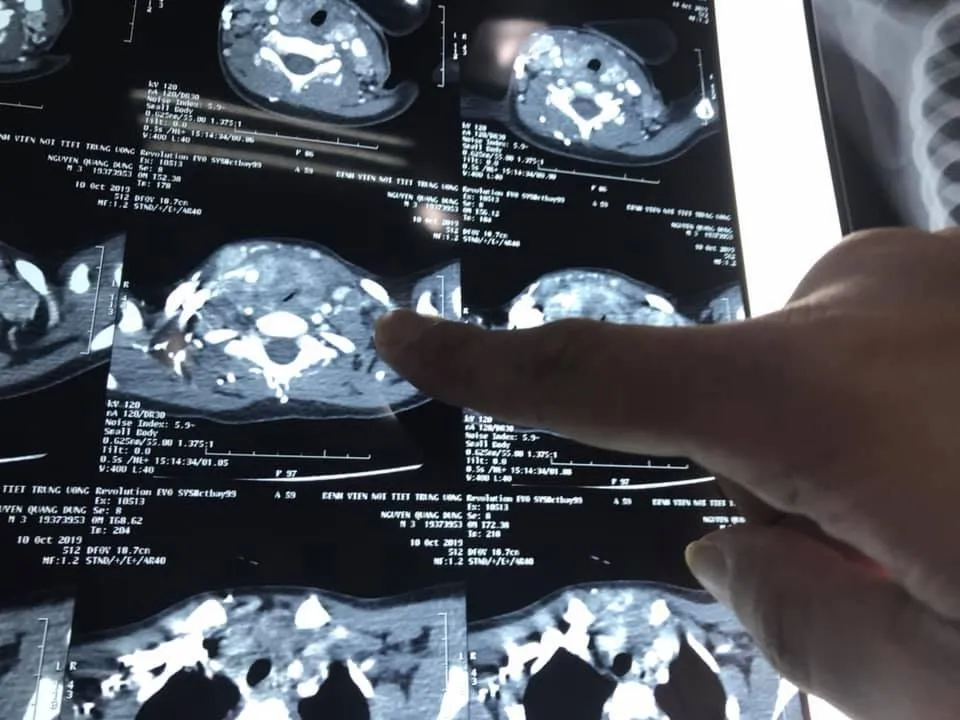

Tại đây, sau khi thực hiện các chỉ định cận lâm sàng, bé D. được chẩn đoán ung thư tuyến giáp với mức độ di căn nhiều hạch cổ 2 bên. Khối u đã phát triển lớn chèn ép khí quản gây khó thở.

Ca phẫu thuật kéo dài hơn 2 giờ đồng hồ do trong quá trình gây mê và phẫu thuật đều gặp rất nhiều khó khăn. Mức độ di căn lan rộng vào cả dây thần kinh quặn ngược, tĩnh mạch cảnh và khí quản gây đè bẹp khí quản khiến cho việc đặt nội khí quản trong quá trình gây mê, quá trình bóc tách, nạo các nhóm hạch ở vùng cổ hết sức khó khăn. Ngoài ra, việc sử dụng liều lượng thuốc như thế nào cũng phải được cân nhắc kỹ lưõng. Đặc biệt, đối với trường hợp nhỏ tuổi như thế này đòi hỏi phẫu thuật viên phải có trình độ chuyên sâu, có kinh nghiệm cả về phẫu thuật mạch máu và nội khí quản mới có thể thực hiện được.

Cũng theo PGS Lương, ngay trong quá trình phẫu thuật, hạch di căn của bé D. đã được đem đi thực hiện cắt lạnh tế bào và cho kết quả ung thư tuyến giáp thể tủy. Đây được coi là thể ít gặp đối với những bệnh nhân nhỏ tuổi trong ung thư tuyến giáp và chỉ có khoảng 5% trường hợp mắc phải.